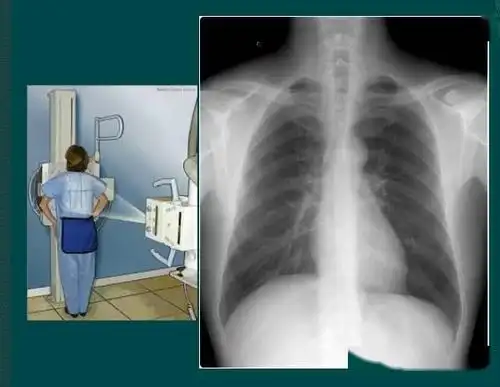

①后前位(posteroanterior view,pa view)投照体位:x线从患者背后穿透